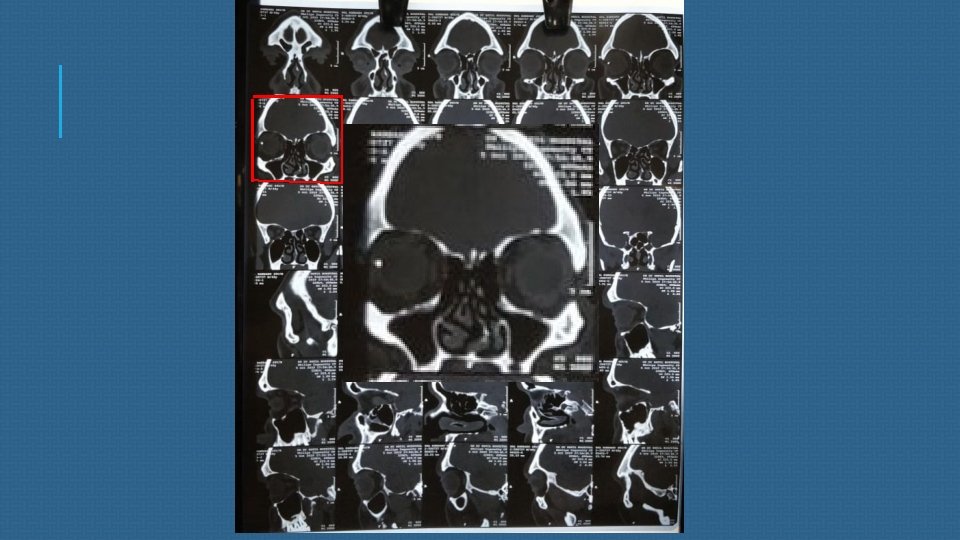

CT scan of brain and orbit S/o –a well defined metallic density, 10 x 4 mm along the lateral aspect of right eyeball/ deep to lateral rectus muscle within the right orbit s/o a foreign body.